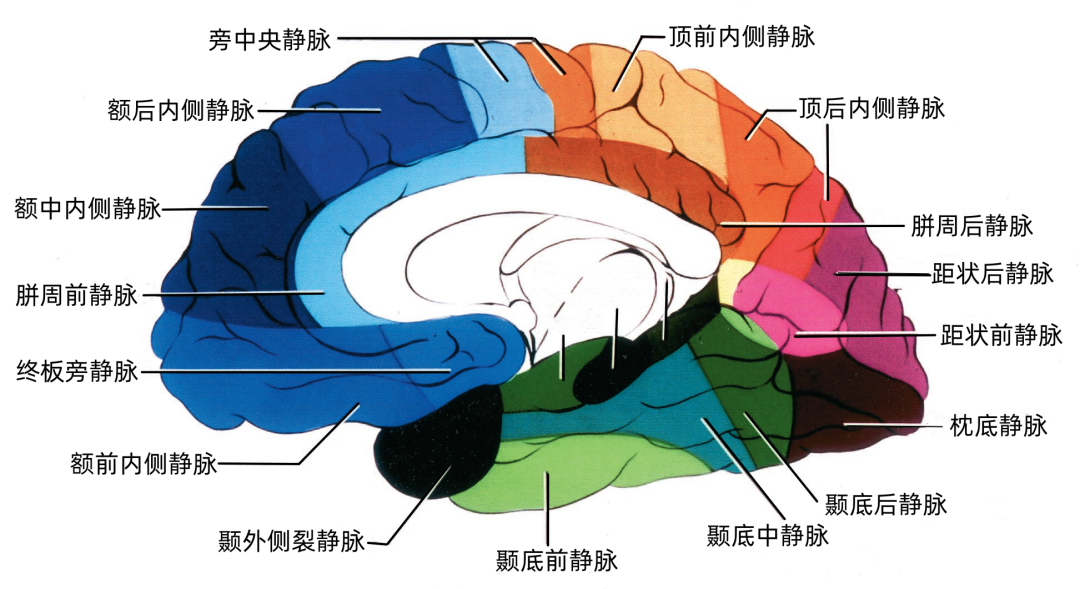

▼2.大脑内侧面静脉的引流区

额叶内侧面(蓝色)由终板旁静脉、额前内侧静脉、额中内侧静脉,额后内侧静脉、胼周前静脉、旁中央静脉引流。

顶叶内侧面(黄色)由旁中央静脉、顶前内侧静脉、顶后内侧静脉、胼周后静脉引流。

枕叶内侧面(紫色)由距状前静脉、距状后静脉引流。

大脑内侧面静脉的引流方向

额叶内侧面的静脉按引流方向由两种蓝色标出:浅蓝色为上升静脉,进入上矢状窦。深蓝色为下降支,汇入下矢状窦和大脑前静脉、基底静脉。

升支包括额前内侧静脉、额中内侧静脉、额后内侧静脉和旁中央静脉。降支包括终板旁静脉和胼周前静脉。

顶叶内侧面的静脉按引流方向由两种红色标出:浅红色为上升静脉,进入上矢状窦。深蓝色为下降支,进入Galen静脉及其属支。

升支包括旁中央静脉、顶前内侧静脉、顶后内侧静脉。降支为胼周后静脉。

枕叶内侧面的静脉按引流方向由两种紫色标出:浅紫色为上升静脉,进入上矢状窦。深紫色为下降支,进入Galen静脉及其属支。

升支包括距状后静脉和进入深静脉系统的距状前静脉。

额叶底面(蓝色)由额极静脉、眶额前静脉、眶额后静脉,嗅静脉和终板旁静脉引流。 颞叶底面(绿色)由颞底前静脉、颞底中静脉、颞底后静脉、海马前静脉、钩回静脉、颞内侧静脉、颞外侧裂静脉。

额叶底面的静脉按引流方向由两种蓝色标出:浅蓝色为前组静脉,进入上矢状窦。深蓝色为后组静脉,进入基底静脉前端。额底静脉的前组是眶额前静脉;后组包括眶额后静脉和嗅静脉。 颞叶底面的静脉按引流方向由两种绿色标出:深绿色标注的静脉向外侧走行汇入小脑幕窦。浅绿色标注的静脉向内侧走行汇入基底静脉。向外侧走行的颞底静脉包括颞底前静脉、颞底中静脉、颞底后静脉;向内侧走行的颞底静脉包括海马前静脉、钩回静脉、颞内侧静脉。 枕叶底面只有一支即枕下静脉,由紫色标出,汇入小脑幕窦。大脑内静脉汇入Galen静脉。

顶叶的静脉根据引流分为顶叶外侧面组和顶叶内侧面组。 引流外侧面的静脉分为上升组和下降组。上升组汇入上矢状窦。下降组流入外侧裂静脉。上升组包括中央沟静脉和中央后静脉,还有顶前、后静脉。下降组由顶外侧裂静脉构成。 静脉及其引流区域如下:中央后静脉引流缘上回前部、顶上小叶和中央后回后部;顶前静脉引流缘上回和角回;顶后静脉引流顶下小叶后部和邻近的枕叶;顶外侧裂静脉引流中央后回和顶下小叶。 顶内侧静脉分为向上汇入上矢状窦的上升组和向下绕过胼胝体压部进入Galen静脉或其属支的下降组。上升组包括旁中央沟静脉、顶前内侧静脉和顶后内侧静脉。下降组为胼周后静脉。顶叶内侧面和外侧面的上升静脉经常在汇入上矢状窦前先在半球上缘汇合。旁中央沟静脉引流相邻的额叶和顶叶,与额内侧静脉一起描述。 顶内侧静脉及其引流区域如下:顶前内侧静脉引流扣带回上缘和楔前叶前部;顶后内侧静脉引流楔前叶后部和邻近的枕叶;胼周后静脉成对,引流胼胝体、扣带回和楔前叶后部。

枕叶的引流静脉分为外侧组、内侧组和底面组。引流颞叶和顶叶后部的静脉可引流枕叶前部。事实上,枕叶外侧面的引流静脉通常行向前方,而不是后方,这就使得在窦汇前方4~5cm的范围内没有枕叶外侧面的静脉直接引流入上矢状窦,枕叶内侧面后部同样如此。 枕叶内侧面由距状前、后静脉引流。距状前静脉(也称为枕内侧静脉)引流楔叶和舌回的前部,距状后静脉引流距状裂的后部。 枕叶底面由枕下静脉引流。枕基底静脉起自舌回下外侧部、邻近的颞枕区和颞下回连接的属支。它向前外侧走向枕前切迹,而且经常在注入小脑幕外侧窦之前与颞基底后静脉汇合。少数静脉向前内侧走行注入基底静脉。

从下表面引流入小脑幕窦的静脉包括颞底前静脉,颞底中静脉、颞底后静脉和枕底静脉。 内侧小脑幕窦接受来自小脑的静脉血流,并加入直窦。基底窦位于斜坡。 大脑镰组(上图 紫色)由直接或经由大脑内静脉、基底静脉和大脑大静脉汇入下矢状窦或直窦的静脉构成。汇入直窦的静脉(上图 紫色)或其属支,引流胼胝体附近部分的额叶、顶叶和颞叶内侧部,此组静脉的引流区域大致相当于大脑边缘叶,包括终板旁静脉,额眶后静脉、嗅静脉、胼周前静脉、胼周后静脉,钩回静脉、海马前静脉、颞内侧静脉和距状前静脉。

终板旁回和嗅旁回的静脉向后引流入大脑前静脉,并最终进入基底静脉前部。扣带回和胼胝体前部由胼周前静脉引流,可能汇入下矢状窦或大脑前静脉。扣带回后部由胼周后静脉引流,最后汇入四叠体池内的大脑大静脉或大脑内静脉。扣带回峡部附近和距状裂前部周围区域由距状前静脉引流,经过四叠体池汇入大脑大静脉或其属支。海马旁回的内侧部和钩回由钩回静脉、海马前静脉和颞中静脉引流,向内侧引流汇入脚间池和环池的基底静脉。 皮层浅静脉并不像通常所说的那样没有规律或变异极大,虽然大多数浅静脉并不沿脑沟走行,但依然可以帮助定位脑沟。 静脉和脑沟关系最密切的是:外侧裂浅静脉和外侧裂,中央沟静脉和中央沟,中央后静脉和中央后沟,顶前内侧静脉和扣带沟升支,顶后内侧静脉和顶枕沟,胼周前,后静脉以及胼胝体沟的前部和后部。在静脉汇入静脉窦的地方,它们与脑沟的毗邻关系变得就不突出了。 在不同的大脑,同一大脑的左右两侧,各皮层浅静脉的大小变异也比较大。大脑外侧面静脉比内侧面和底面的静脉粗大。大脑外侧面最大的静脉通常位于中央沟附近。 大脑外侧的静脉就像车轮的辐条一样排列,从外侧裂的主干向外辐射。皮层外侧三条最大的回流路径分别是Trolard静脉、Labbé静脉和外侧裂浅静脉。主要由Labbé静脉引流的例数,优势半球是非优势半球的两倍;而在非优势半球,Trolard静脉有类似比例。 事实上,牺牲某单支静脉并不经常造成静脉性梗塞、出血、水肿和神经功能障碍,这主要与静脉之间的吻合有关。相邻区域的皮层静脉、浅静脉、深静脉和脑池静脉之间存在丰富吻合支,在大脑半球外侧面、内侧面和底面的边缘也有许多吻合支引流邻近的部分。 在一些手术入路中,烧闭浅的桥静脉或深的桥静脉,包括大脑大静脉、基底静脉和大脑内静脉是无法避免的;但对于这些静脉及其属支的破坏应尽量减少,因为它可能造成严重的后果。另一种选择是仅切断一些小的属支,而将主干牵拉出术野。如果暴露时发现桥静脉较正常的粗大,手术时要尽量保留。 静脉增大提示其引流范围增大,损伤它们可能导致严重后果的几率增加。在一些病例中,粗大的Labbé或Trolard静脉或外侧裂浅静脉可能引流大脑半球外侧的大部。阻断由几条皮层静脉形成的桥静脉,较牺牲单个静脉末端形成的桥静脉或皮层支造成的后果要严重。